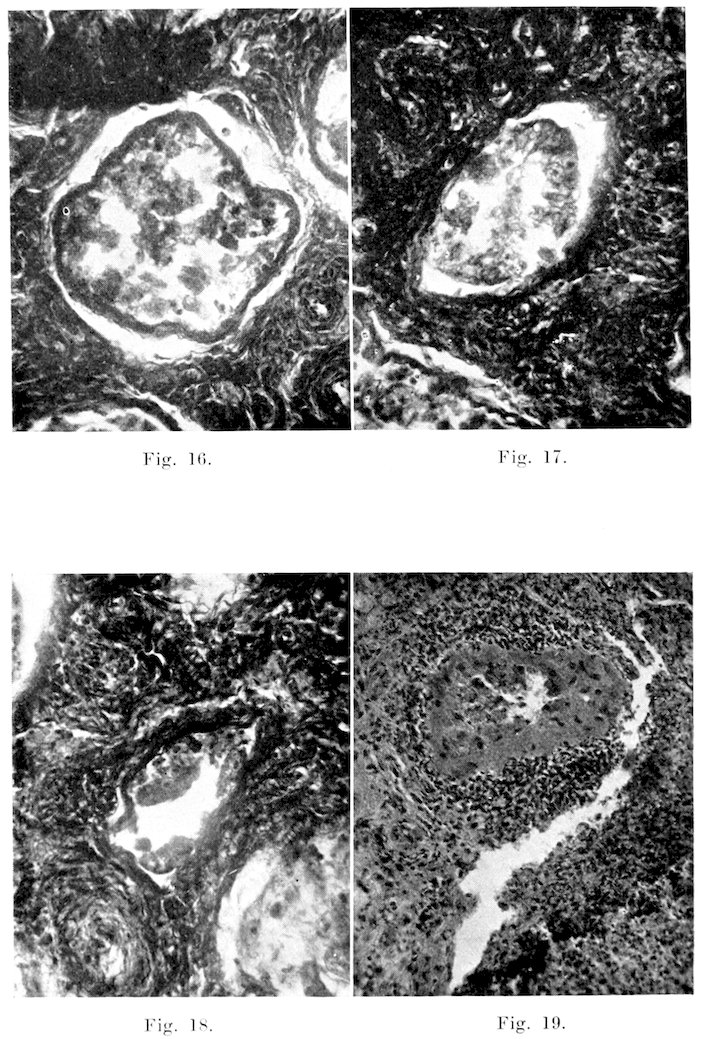

294. The Peri-vesicular or “pan-inflammatory” Type usually is the result of severe inflammation of the vesicles, with probable rupture of some of the smaller cysts or abscesses upon the surface. The vesicles are, as a rule, considerably enlarged and buried in a dense mass of adhesions which involve neighboring structures. The vesicles cannot be palpated on physical examination, and it is only on careful post mortem dissection that they may be studied. This type, however, is quite rare,—two cases only having come to my attention. In both, the vesicles themselves were markedly affected.

Microscopically, changes in the vesicles are quite frequently encountered, even in the absence of gross manifestations. In the acute catarrhal forms, the mucosa and submucosa are hyperaemic. The lining cells show various forms of degeneration, and there are, as a rule, inflammatory exudates in the lumen. As the inflammation progresses, the lining cells degenerate further, and become cast off into the lumen of the glandular cavities, as in Plate VI. The normal clear mucous secretion becomes mixed with fibrin, leucocytes, and cellular debris. These changes may involve merely parts of the organ, or they may be quite extensive. With large sections, one may find the inflammation in all stages, from the mildest catarrhal type, to complete degeneration and exfoliation of the secretion-forming mucosal cells, and filling of the cavities with degenerated cells, leucocytes, and debris. Frequently the interstitial tissue is in no way affected, but at times it is thickened by oedematous exudates, leucocytes, and fibrin. The chronic interstitial form is characterized by a considerable increase of connective tissue,—producing marked atrophy, or even complete obliteration of the glandular cavities. Microscopically the suppurative form may be diffuse over the entire gland, or as stated previously, may be in the form of localized abscesses, with or without a thick connective tissue wall. The parenchyma in these cases is usually extensively degenerated and atrophied in those parts that have not undergone suppuration and necrosis. The cysts appear to be of the ordinary retention type, and may or may not be accompanied by extensive changes in the lining epithelium.

Both the abscess formation and cystic conditions are undoubtedly initiated by an obstructive inflammation of all or part of the excretory duct. This is, however, a protective mechanism, for where the duct is closed the bacteria and exudates are unable to reach the urethra and contaminate the semen.

Prostate and Cowper’s Glands: These glands were more or less neglected in the early part of the work, but later were subjected to the same examination as other parts. Of the thirty-six of each type of gland examined, I failed to find one with any gross changes, but two prostates were found that presented a mild catarrhal inflammation of the mucosa. It is probable that Cowper’s glands, as well, occasionally undergo inflammatory changes.